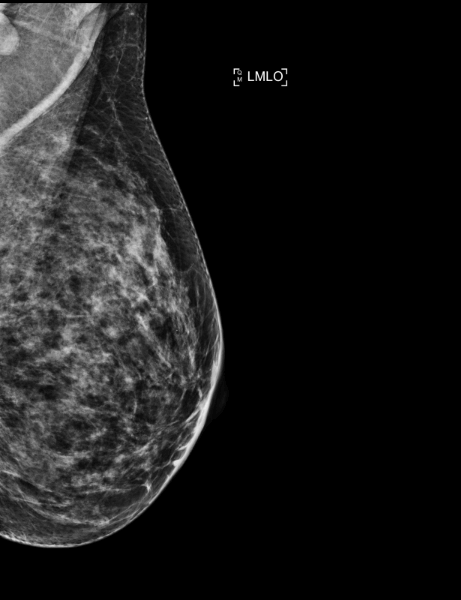

A 40-year-old patient with a history of right breast carcinoma 10 years ago – a routine mammogram was performed.

Mammoscreen® detects an increased opacity in the upper-outer quadrant of the right breast.

Ultrasound shows a hypoechogenic lesion, while the biopsy confirms an adenocarcinoma SBR III; HER2- RH+.